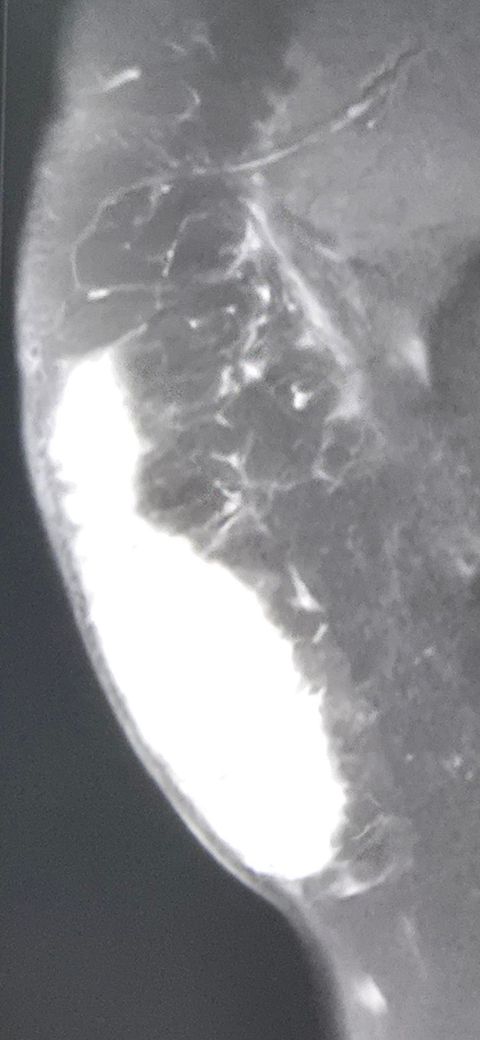

마취도 하면 무슨마취 하나요.. 하반신 마취..? 그리구 이거 제거 하고 무슨 팩주머니 달아준다고 하는데 그 팩 주머니 제거 하고 나서 꿰매겠죠..? 이런거 처음이라 너무 무서워서 그러는데 자세히점 알려주세요ㅠㅠ 사진은 mri 찍은 사진이예요 피만 차고 다른건 다 괜찮다고 하셔서

• 1번 째 사진